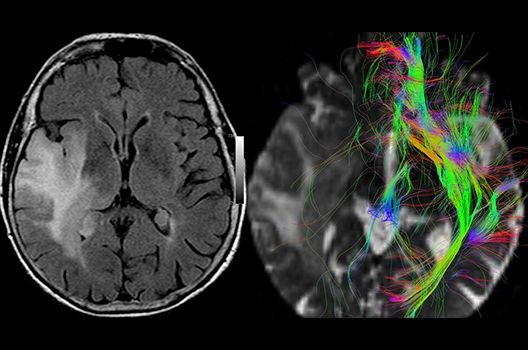

Die Schwerpunkte in der MR-Forschung liegen in der multiparametrischen und funktionellen Bildgebung bei onkologischen und anderen, neuroradiologischen Fragestellungen und umfassen die Anwendung modernster MR-Verfahren sowie die Untersuchung an Hochfeld-Geräten.

Die Magnetresonanztomographie (MRT) ist ein Verfahren, bei dem durch magnetische Kräfte Bilder des Körperinneren angefertigt werden. In der Neuroradiologie können manchmal kleinste Veränderungen schwere Folgen haben; daher forschen wir an der Entwicklung hochauflösender MRT-Sequenzen, mit denen diese Prozesse und auch einzelne Nervenfaserbahnen sichtbar gemacht werden können. Darüber hinaus sind bei vielen Erkrankungen des Gehirns die Blutgefäße betroffen. Daher arbeiten wir an der Neu- und Weiterentwicklung von MRT-Sequenzen zur Darstellung der Blutgefäße und zur Blutflussanalyse (sog. „Angio-MRT“). Einen besonderen Forschungsschwerpunkt unserer Klinik stellen die MR-Protonenspektroskopie und die funktionelle MRT dar, mit denen die Analyse einzelner chemischer Substanzen im Hirngewebe oder die Darstellung ausgewählter Hirnfunktionen möglich ist.